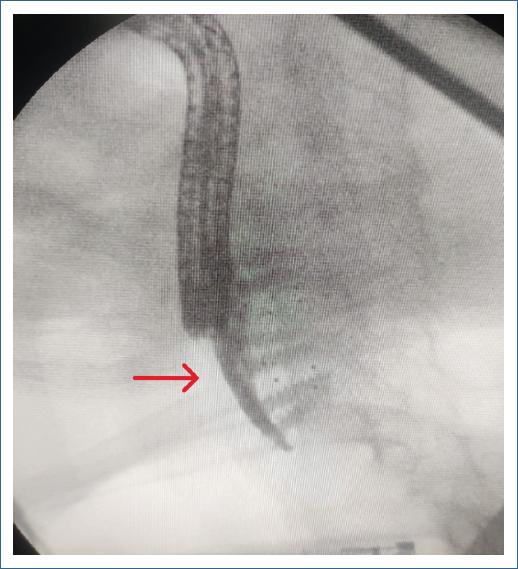

Mujer de 64 años de edad con antecedente de abordaje anterior cervical con colocación de material protésico a nivel de C5-C7 hace seis años por patología degenerativa de la columna cervical, donde se produce una perforación esofágica, la cual es manejada con cierre primario + gastrostomía en el mismo acto quirúrgico; a los pocos días del posquirúrgico presenta fistula esófago-cutánea con gasto siálico, el cual se maneja de forma conservadora (Figs. 1 y 2). Ante el cese de gasto de fistula se inicia tolerancia de alimentos con adecuada respuesta; a los dos años presenta leve disfagia a sólidos, para lo cual se realiza panendoscopia de control, la cual reporta estenosis 20% franqueable a nivel de cricofaríngeo. La paciente continúa con valoraciones frecuentes de manera anual por parte del servicio de endoscopia, sin embargo, ante la presencia de mayor disfagia a sólidos y en el último mes a líquidos, se realiza valoración endoscópica a los seis meses de su último control donde se identifica estenosis esofágica 50% + material de osteosíntesis en la luz esofágica a nivel del cricofaríngeo, hallazgo no encontrado en su último control (Fig. 3). Paciente al momento de su valoración hemodinámicamente estable, sin respuesta inflamatoria, sin sepsis, sin dolor; sin embargo, con alto riesgo de osteomielitis a nivel cervical, por lo cual se envía al servicio de cirugía de columna para valoración de los hallazgos descritos.

Figura 1 Presencia de placa cervical por fluoroscopio.